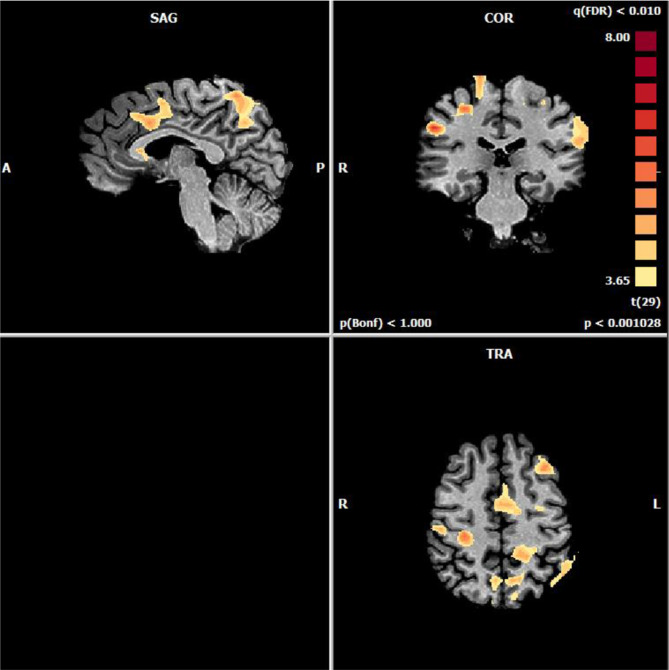

Results: Average ratings did not differ from IADS-2 norms. Pleasant sounds significantly activated brain regions implicated in reward and positive affect, including the mPFC, ventral anterior cingulate cortex, and inferior frontal gyrus, compared to neutral sounds. Alternatively, unpleasant sounds elicited stronger and more widespread activation, particularly in the amygdala, nucleus accumbens, insula, and cerebellum, regions associated with negative affect and aversive learning.

Conclusion: These results demonstrate the pivotal contributions of the amygdala in identifying unpleasant stimuli and of the mPFC in assessing pleasant auditory inputs, expand our current understanding of affective regulation at the neural circuit level, and provide a foundation for the development of sound-based interventions to treat auditory-emotional disorders such as misophonia and anxiety.